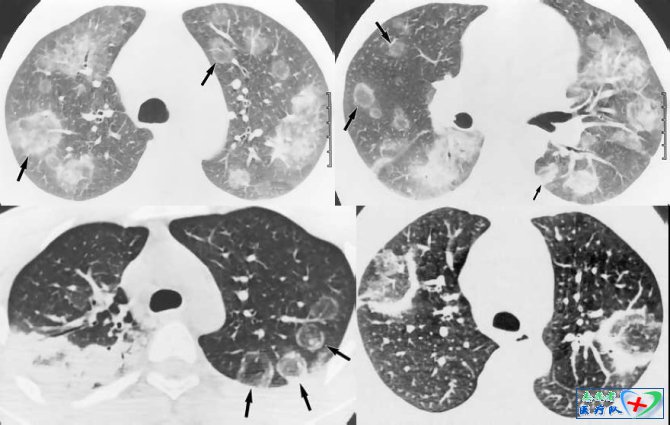

2、多结节聚合征

胸部高分辨CT扫描时,这种表现有三种表现:花瓣状、桑椹样和葫芦状。花瓣状病灶一般直径在2公分以内,纵隔窗下可见由3~5个1~5mm的小结节聚合而成,每个小结节之间有低密度分隔,形如花瓣;桑葚样病灶大于2公分,由10个左右的小结节聚合而成;葫芦状结构呈多个椭圆形堆彻排列,胸膜侧的结节最大,直径可达3~5公分,其内密度较低,近肺门侧直径较小,直径约1.5公分,形如葫芦状。花瓣状聚合被认为是周围性肺癌的早期表现;桑葚样多结节聚合征可能是小叶间隔纤维增生,肺癌各部生长不一,肿瘤生长遇到阻力;葫芦样结节被认为是肿瘤组织以连续浸润方式进行扩散,由于肿瘤不断增大,从原发肿瘤脱落下来的流组织经组织间隙、淋巴管、血管等侵入并破坏周围正常组织且继续生长(肿瘤成团的充满肺泡腔,并沿肺泡空向周围继续生长,膨胀性扩大)或肿瘤沿肺泡壁伏壁生长,都可以形成此征。